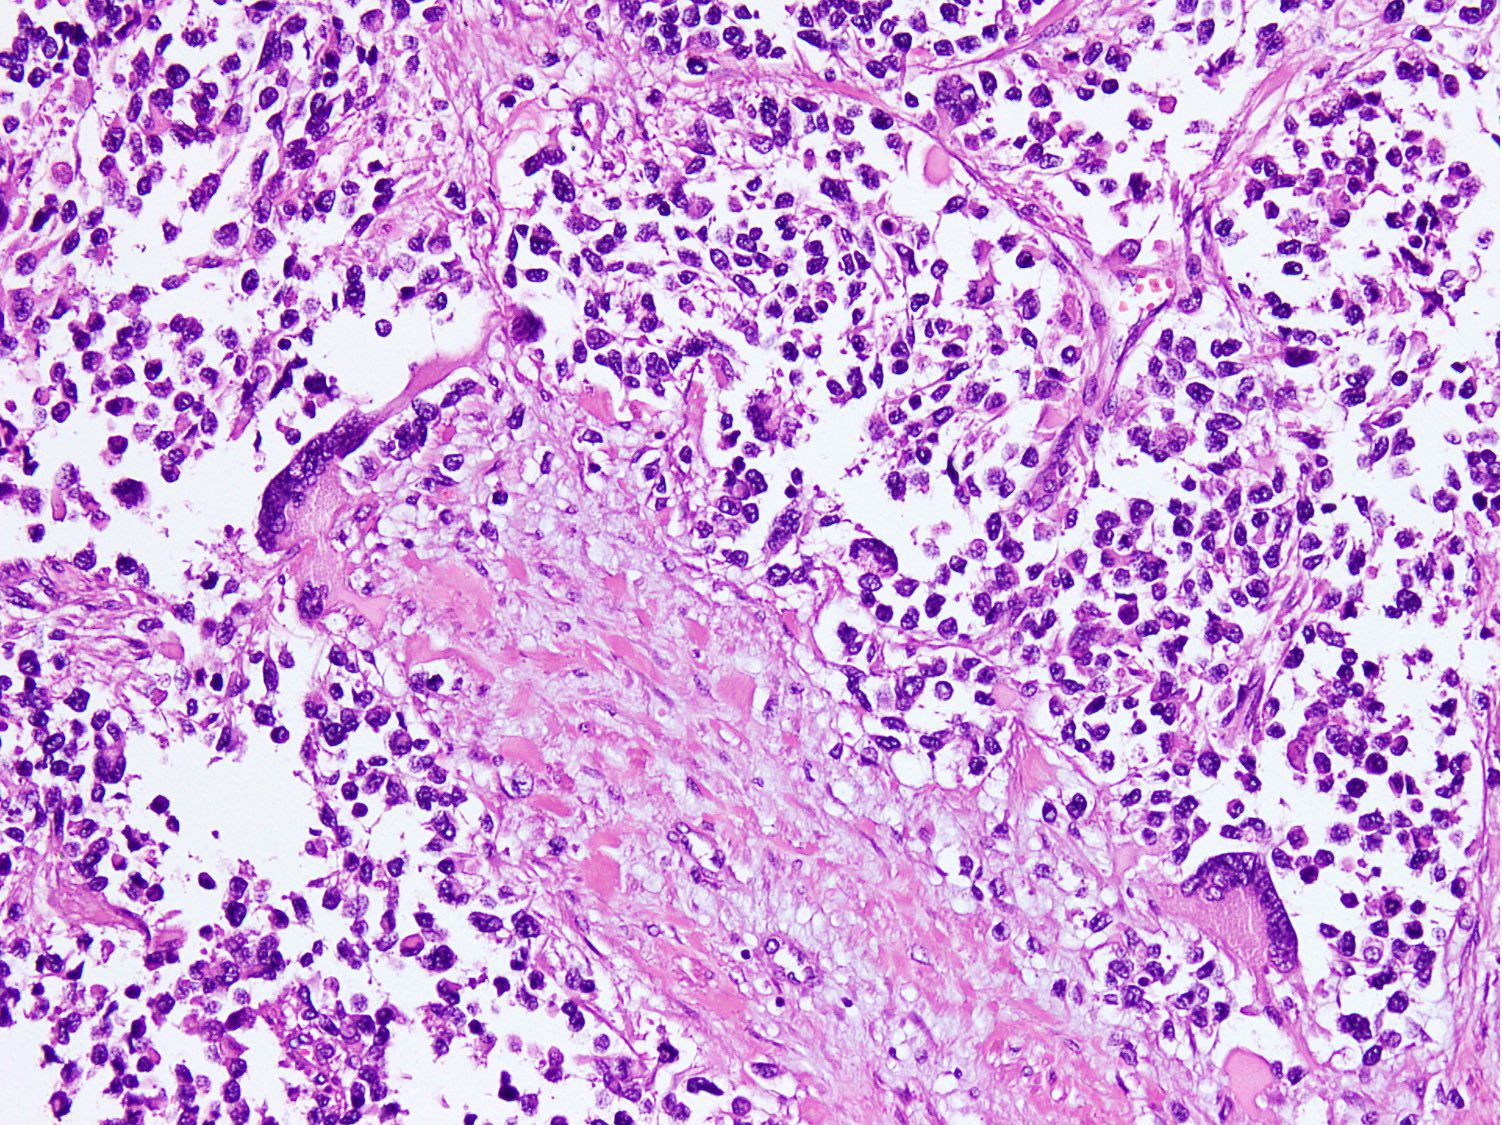

Microscopic (histologic) description

- Cellular round cell tumor

- Cells in the center have poor preservation and are necrotic; may appear floating

- Multinucleated tumor giant cells with wreath-like lineup of nuclei are common (Acta Pathol Microbiol Immunol Scand A 1982;90:345)

- Round to oval rhabdomyoblasts with abundant acidophilic cytoplasm may be present

- Brisk mitosis and variable tumor necrosis

- Occasional cases may show clear cell morphology with pale, glycogenated cytoplasm

- Rare anaplasia

- Solid variant:

- Sheets of neoplastic cells

- Lack fibrovascular septa, pseudoalveolar spaces and dyscohesion (Cancer Genet Cytogenet 2005;163:138)

- May show rhabdomyoblastic differentiation

- Abundant mitotic activity

Microscopic (histologic) images

Contributed by Nasir Ud Din, M.B.B.S.

- Comment: Histology shows an infiltrative cellular tumor composed of large clusters and nests of primitive round cells, separated by variably thick fibrovascular septa. Irregular pseudoalveolar spaces and cystic change are present within the nests. Scattered wreath-like multinucleated giant cells and rhabdomyoblasts are present along with brisk mitosis and necrosis. Tumor cells show strong and diffuse desmin and myogenin expression, focal MyoD1 and alpha smooth muscle actin positivity, whereas CD34, S100, CK AE1 / AE3, CD99, SALL4, LCA, TdT and synaptophysin are negative. Morphological features and immunoprofile strongly support the diagnosis of alveolar rhabdomyosarcoma. It is a malignant high grade soft tissue sarcoma with myogenic differentiation and an overall worse prognosis.